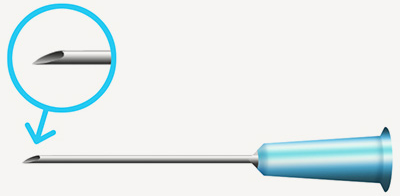

일반니들 (주사침)

끝이 뾰족한 주삿바늘로 주변에서 흔히 볼 수 있는 주삿바늘입니다.

세밀하고 정밀한 결과를 나타내기에 적합하지만 멍이나부기 그리고

필러 내용물이 혈관을 막아버리는 부작용이 발생할 수 있습니다. -